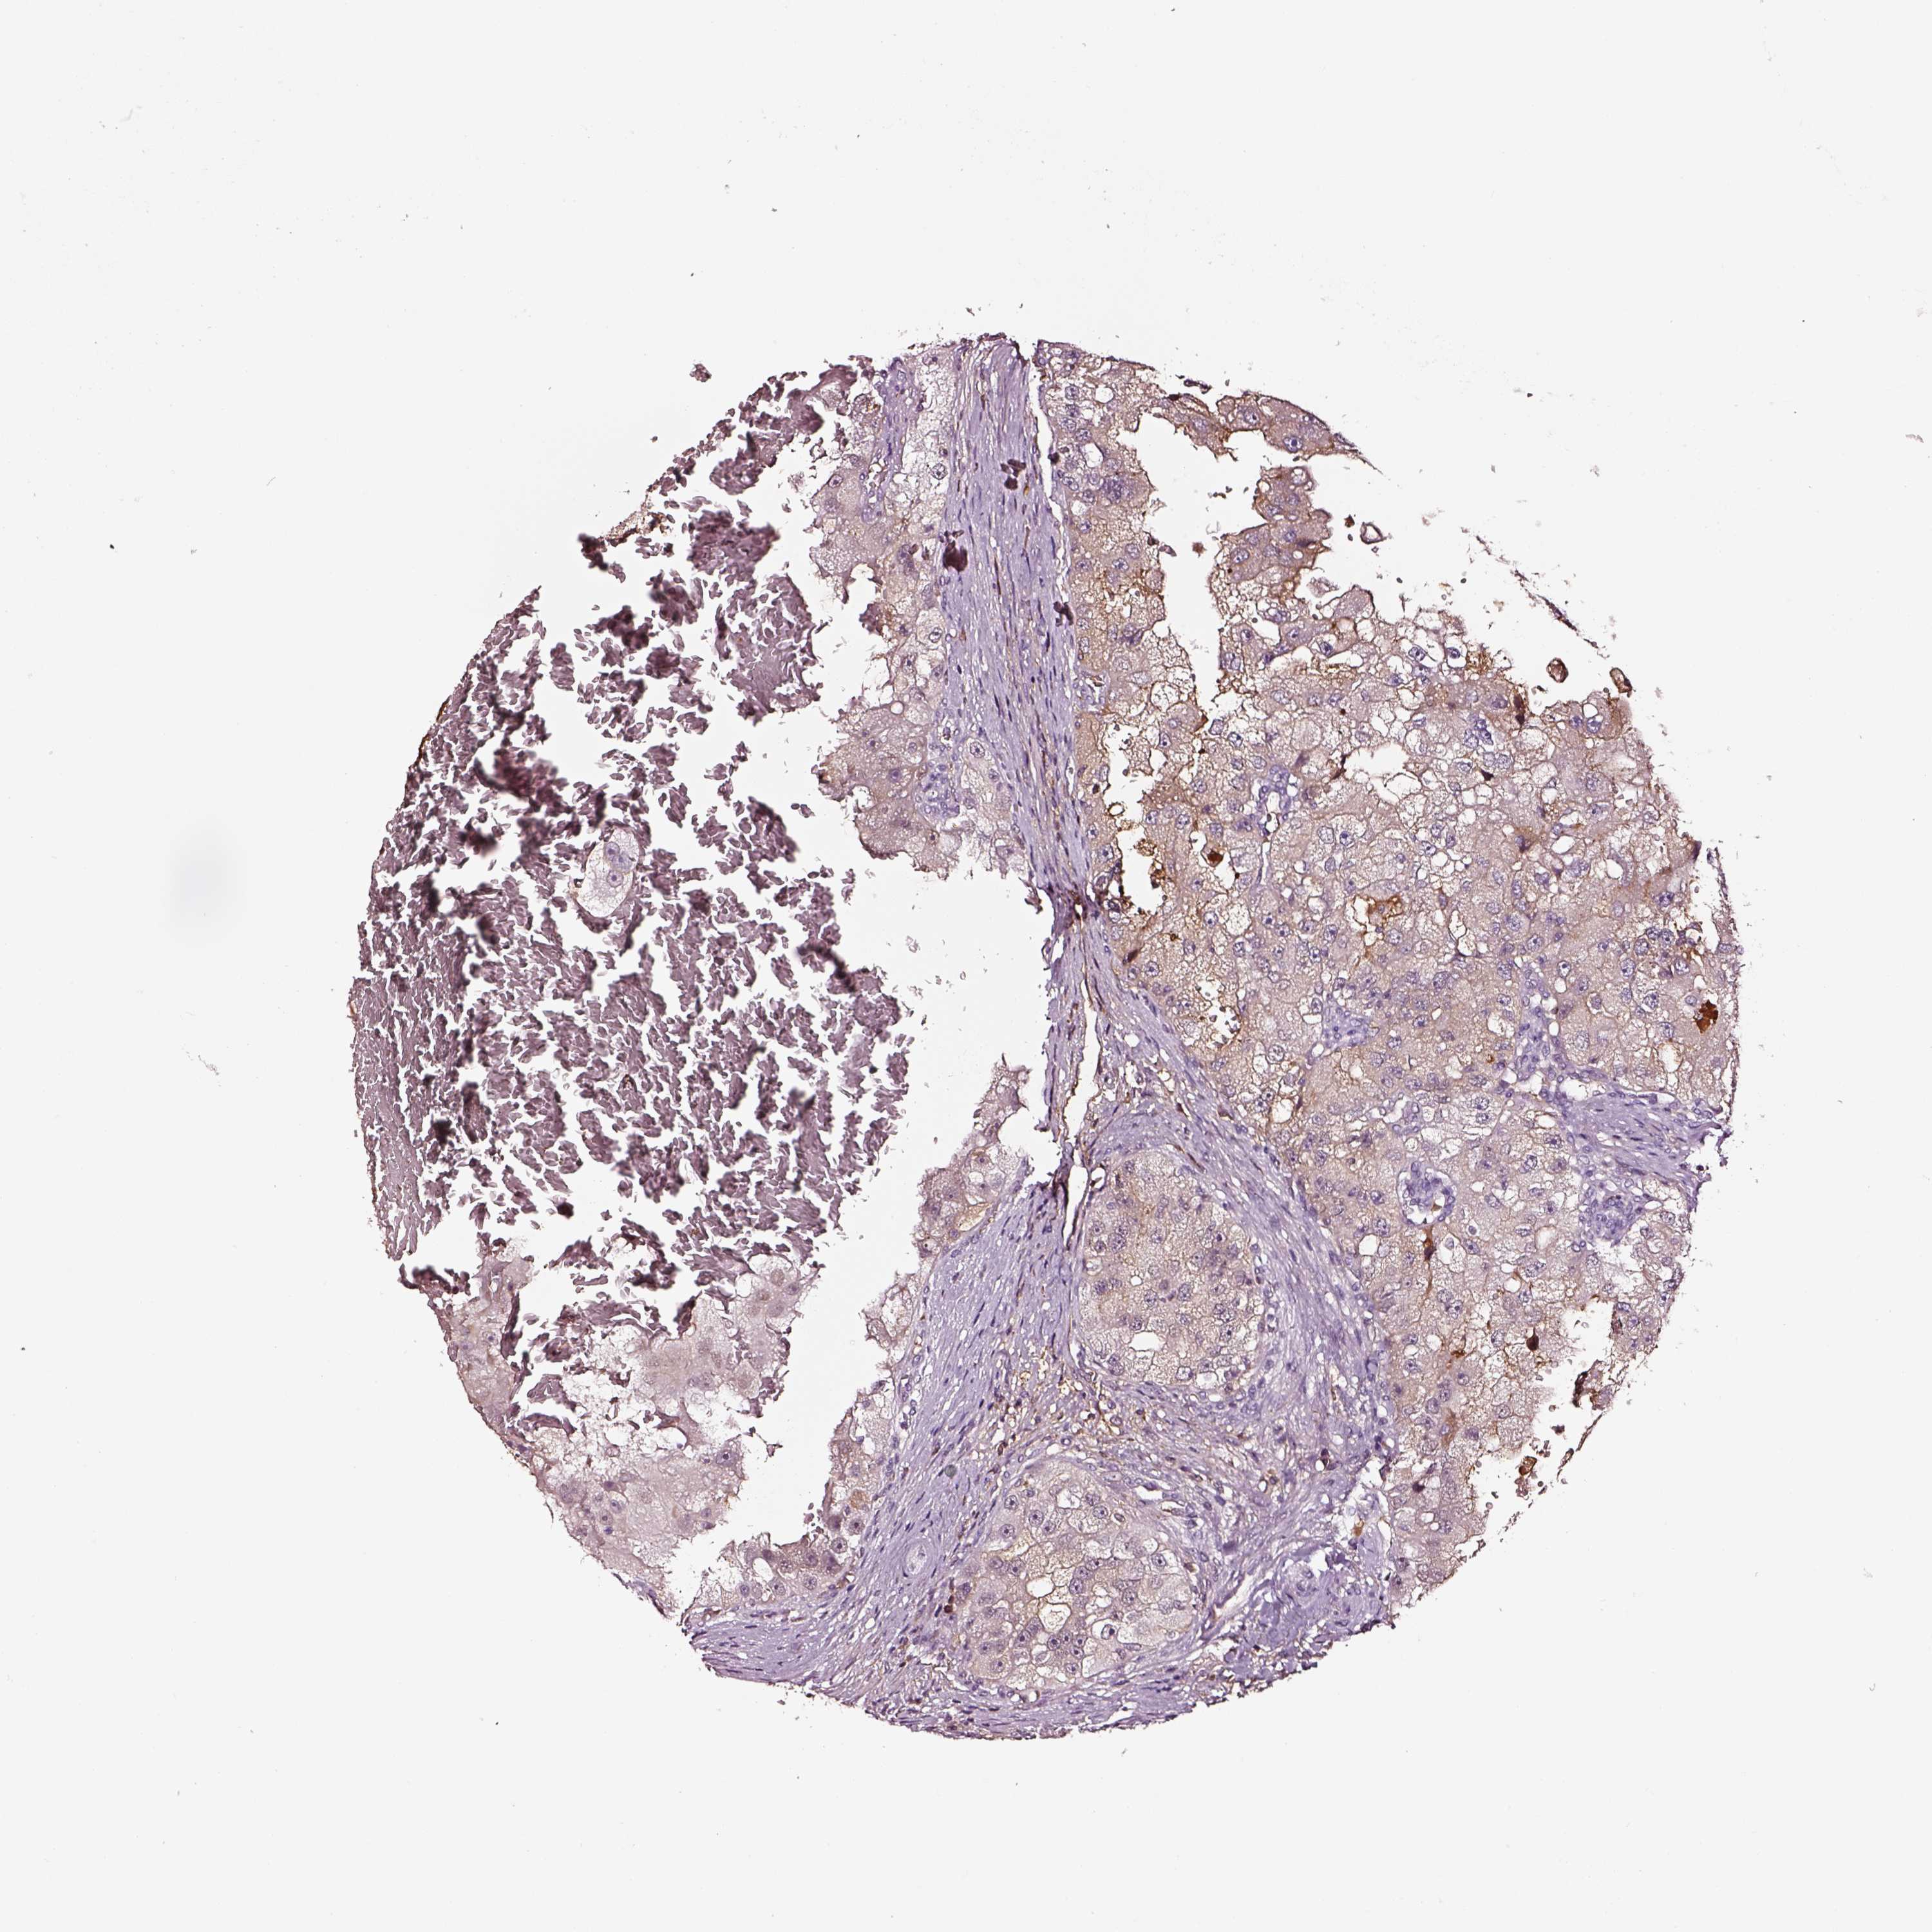

KIDNEY RENAL CLEAR CELL CARCINOMA (VALIDATION) - Interactive survival scatter ploti

The Survival Scatter plot shows the clinical status (i.e. dead or alive) for all individuals in the patient cohort, based on the same data that underlies the corresponding Kaplan-Meier plots. Patients that are alive at last time for follow-up are shown in blue and patients who have died during the study are shown in red.

The x-axis shows the expression levels (FPKM) of the investigated gene in the tumor tissue at the time of diagnosis. The y-axis shows the follow-up time after diagnosis (years). Both axes are complimented with kernel density curves demonstrating the data density over the axes. The top density plot shows the expression levels (FPKM) distribution among dead (red) and alive patients (blue). The right density plot shows the data density of the survived years of dead patients with high and low expression levels respectively, stratified using the cutoff indicated by the vertical dashed line through the Survival Scatter plot. This cutoff is automatically defined based on the FPKM cutoff that minimizes the p-score. The cutoff can be changed by dragging the vertical line or by entering a cutoff value in the square labeled "Current cut-off".

Under the Survival Scatter plot the p-score landscape (black curve; left axis) is shown together with dead median separation (red curve; right axis). Dead median separation is the difference in median mRNA expression between patients who have died with high and low expression, respectively. It is calculated as follows: median FPKM expression of dead patients with high expression - median FPKM expression of dead patients with low expression. This is intended to aid the user in visually exploring custom cutoffs and the associated p-scores and dead median separation.

Individual patient data is displayed and can be filtered by clicking on one or more of the category buttons on the top of the page. Categories describing expression level and patient information include: high, low, alive, dead, female, male and tumor stages. The scale of the x-axis can be toggled between linear and log-scale by clicking on the "x log" button. Mouse-over function shows TCGA ID, patient information and mRNA expression (FPKM) for each patient.

& Survival analysisi

Kaplan-Meier plots summarize results from analysis of correlation between mRNA expression level and patient survival. Patients were divided based on level of expression into one of the two groups "low" (under cut off) or "high" (over cut off). X-axis shows time for survival (years) and y-axis shows the probability of survival, where 1.0 corresponds to 100 percent.

TF is not prognostic in Kidney Renal Clear Cell Carcinoma (validation)

Best expression cut offi

Based on the FPKM value of each gene, patients were classified into two groups and association between prognosis (survival) and gene expression (FPKM) was examined. The best expression cut-off refers the FPKM value that yields maximal difference with regard to survival between the two groups at the lowest log-rank P-value. Best expression cut-off was selected based on survival analysis .

When clicking on this number, the vertical dashed line indicating cut-off, the interactive survival plot, and the Kaplan-Meier curve will be adjusted to show results based on the best expression cut-off.

: 1.65

TCGA RNA samplesi

RNA-seq data is reported as average FPKM (number Fragments Per Kilobase of exon per Million reads), generated by the The Cancer Genome Atlas (TCGA) .

Normal distribution across the dataset is visualized with box plots, shown as median and 25th and 75th percentiles. Points are displayed as outliers if they are above or below 1.5 times the interquartile range. FPKM values of the individual samples are presented next to the box plot.

Average pTPM 14.7

Number of samples 100